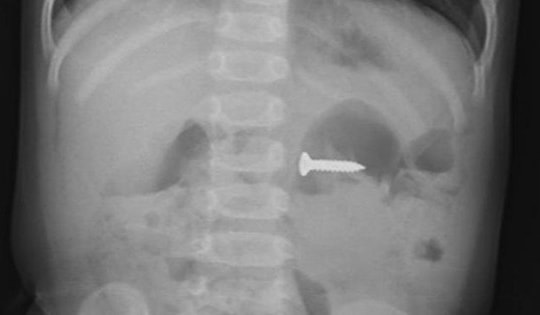

Gắp đinh vít dài 4 cm trong dạ dày bé trai 3 tuổi ở Quảng Ngãi

Trải qua 30 phút, ekip nội soi đã gắp thành công dị vật là cây đinh vít dài 4cm từ trong dạ dày của bé trai 3 tuổi ra ngoài.